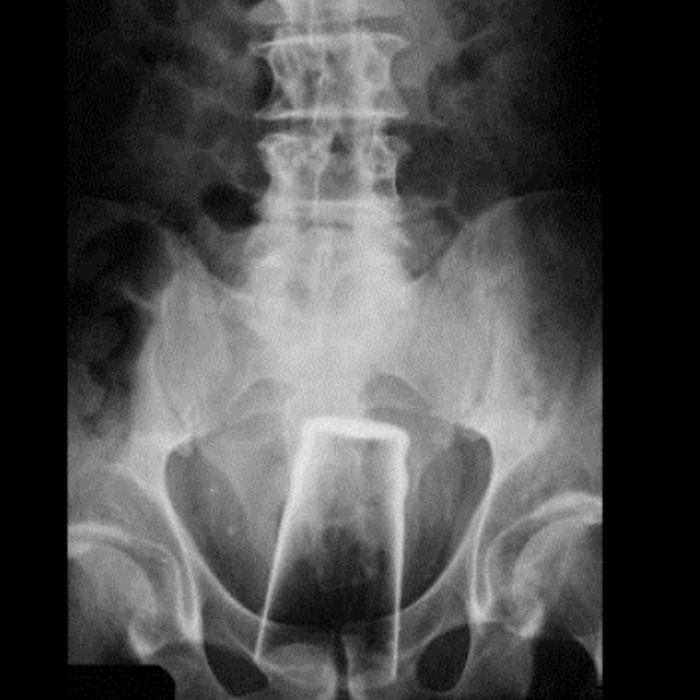

It might be hard to see, but that’s a Buzz Light Year. Part of me was sceptical on how it could even get in there in the first place (there’s lots of pointy party), but then I remembered the rest of the list.